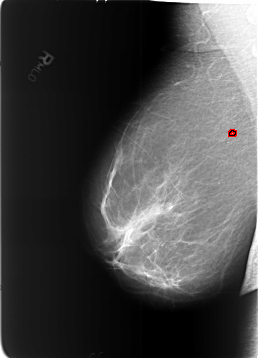

FILE: B_3453_1.RIGHT_MLO.OVERLAY

TOTAL_ABNORMALITIES 1

ABNORMALITY 1

LESION_TYPE CALCIFICATION TYPE SKIN DISTRIBUTION REGIONAL

ASSESSMENT 2

SUBTLETY 3

PATHOLOGY BENIGN_WITHOUT_CALLBACK

TOTAL_OUTLINES 1

BOUNDARY